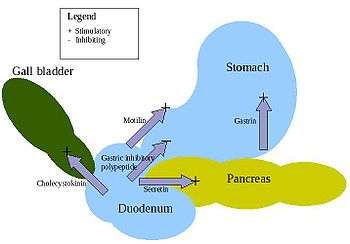

The stomach is a major organ of the gastrointestinal tract and digestive system. It is a consistently J-shaped organ joined to the esophagus at its upper end and to the duodenum at its lower end. Gastric acid (informally gastric juice), produced in the stomach plays a vital role in the digestive process, and mainly contains hydrochloric acid and sodium chloride. A peptide hormone, gastrin, produced by G cells in the gastric glands, stimulates the production of gastric juice which activates the digestive enzymes. Pepsinogen is a precursor enzyme (zymogen) produced by the gastric chief cells, and gastric acid activates this to the enzyme pepsin which begins the digestion of proteins. As these two chemicals would damage the stomach wall, mucus is secreted by innumerable gastric glands in the stomach, to provide a slimy protective layer against the damaging effects of the chemicals.

Gallbladder

The gallbladder is a hollow part of the biliary system that sits just beneath the liver, with the gallbladder body resting in a small depression.[26] It is a small organ where the bile produced by the liver is stored, before being released into the small intestine. Bile flows from the liver through the bile ducts and into the gall bladder for storage. The bile is released in response to cholecystokinin (CKK) a peptide hormone released from the duodenum. The production of CKK (by endocrine cells of the duodenum) is stimulated by the presence of fat in the duodenum.[27]

The pancreas is a major organ functioning as an accessory digestive gland in the digestive system. It is both an endocrine gland and an exocrine gland.[28] The endocrine part secretes insulin when the blood sugar becomes high; insulin moves glucose from the blood into the muscles and other tissues for use as energy. The endocrine part releases glucagon when the blood sugar is low; glucagon allows stored sugar to be broken down into glucose by the liver in order to re–balance the sugar levels. The pancreas produces and releases important digestive enzymes in the pancreatic juice that it delivers to the duodenum. The pancreas lies below and at the back of the stomach. It connects to the duodenum via the pancreatic duct which it joins near to the bile duct's connection where both the bile and pancreatic juice can act on the chyme that is released from the stomach into the duodenum. Aqueous pancreatic secretions from pancreatic duct cells contain bicarbonate ions which are alkaline and help with the bile to neutralise the acidic chyme that is churned out by the stomach.

The pancreas is also the main source of enzymes for the digestion of fats and proteins. Some of these are released in response to the production of CKK in the duodenum. (The enzymes that digest polysaccharides, by contrast, are primarily produced by the walls of the intestines.) The cells are filled with secretory granules containing the precursor digestive enzymes. The major proteases, the pancreatic enzymes which work on proteins, are trypsinogen and chymotrypsinogen. Elastase is also produced. Smaller amounts of lipase and amylase are secreted. The pancreas also secretes phospholipase A2, lysophospholipase, and cholesterol esterase. The precursor zymogens, are inactive variants of the enzymes; which avoids the onset of pancreatitis caused by autodegradation. Once released in the intestine, the enzyme enteropeptidase present in the intestinal mucosa activates trypsinogen by cleaving it to form trypsin; further cleavage results in chymotripsin.